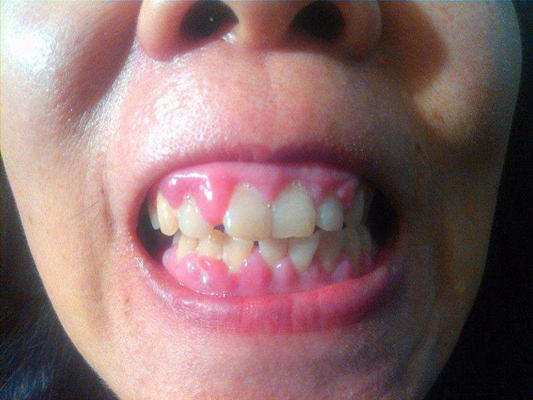

牙齦炎圖片

牙齦炎和牙周炎